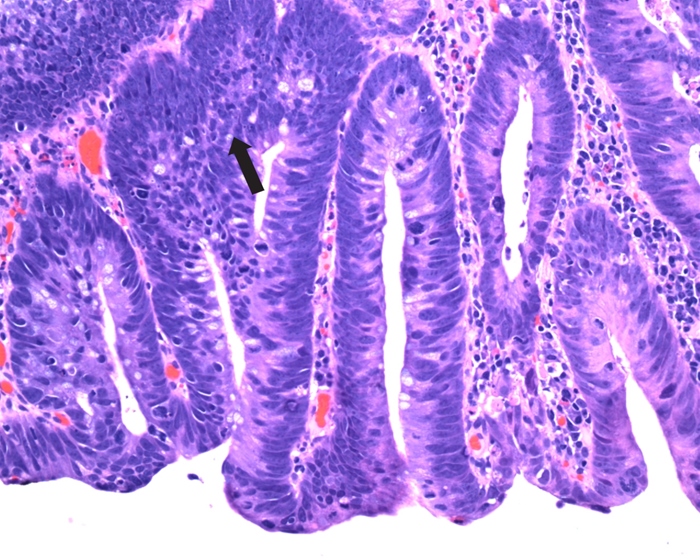

Melanosis Coli

Melanosis coli can develop within a few months of the onset of regular laxative ingestion and can similarly disappear if laxative use is discontinued. If melanosis coli is not seen on gross inspection, histological examination may demonstrate the pigment in the macrophages of the lamina propria.

Diagnosis is supported by a positive stool screen for diphenolic (eg, bisacodyl) or polyethylene-containing laxatives.